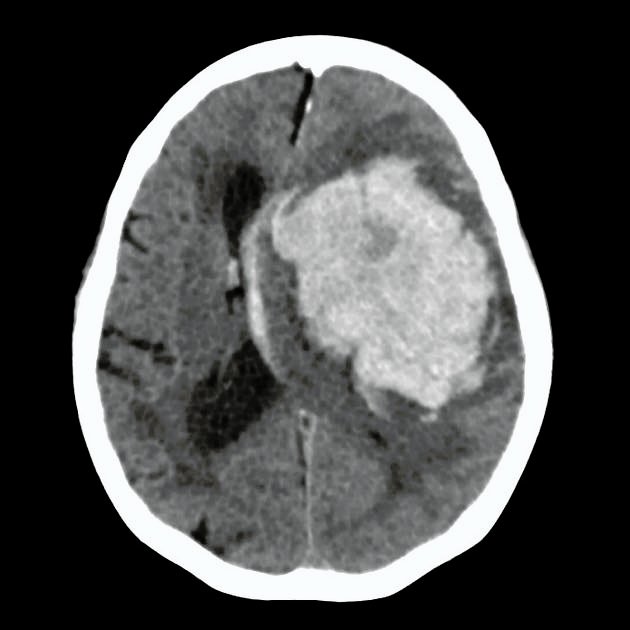

- Non-contrast CT: first-line, hyperdense blood

- CT Angiography (CTA): vascular anomalies, “spot sign” predicts expansion

- Large hematoma volume 🧠

- Intraventricular extension